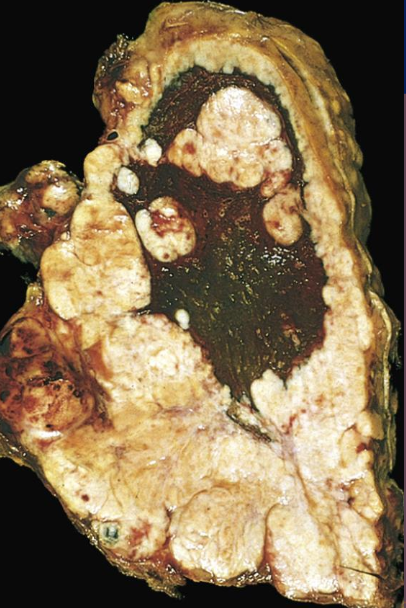

Carcinoma de células grandes, macroscopia

Tumores grandes con necrosis y hemorragia

<p>Carcinoma de células grandes, microscopia</p>

Carcinoma de células grandes, microscopia

• Núcleos grandes

• Nucleolos prominentes

• Moderada cantidad de citoplasma